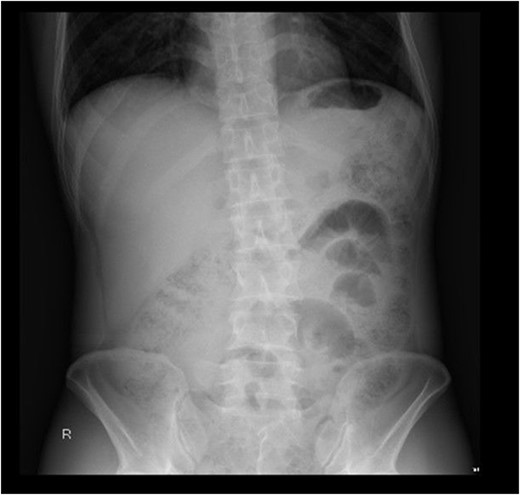

On initial presentation the patient was pyrexial, with a fever of 38.9 °C, but haemodynamically stable. Abdominal examination revealed diffuse peritonitis. Laboratory results showed a mild lecuocytosis (white cell count 10.5 g/L) but were otherwise within normal limits. Plain film X-ray of his abdomen was suggestive of pneumoperitoneum (see Fig. 1). A clinical diagnosis of suspected perforated duodenal ulcer was made and the patient was initially resuscitated with intravenous fluids and broad-spectrum antibiotics while a computed tomography (CT) scan of his abdomen and pelvis was arranged. The CT revealed showed a small rod-shaped radiopaque object in a thickened small bowel loop in the hypogastric region, with associated free abdominal fluid and air (see Fig. 2). This was concerning for small bowel perforation due to a foreign body.

CT scan of abdomen and pelvis. A radiopaque object is seen extruding from a thickened small bowel loop with associated free peritoneal fluid, concerning for foreign body perforation of small bowel.